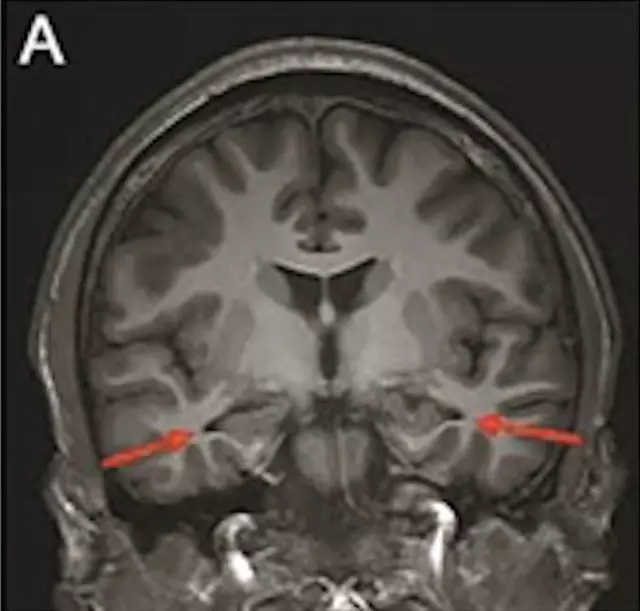

最年輕的19歲阿茲海默症男子腦部掃描結果:

該名19歲男子到醫院接受多項檢查,包括腦脊液指標檢測及正電子掃描。結果顯示,他出現輕度腦萎縮等症狀,最終被臨床診斷為「阿茲海默症」。